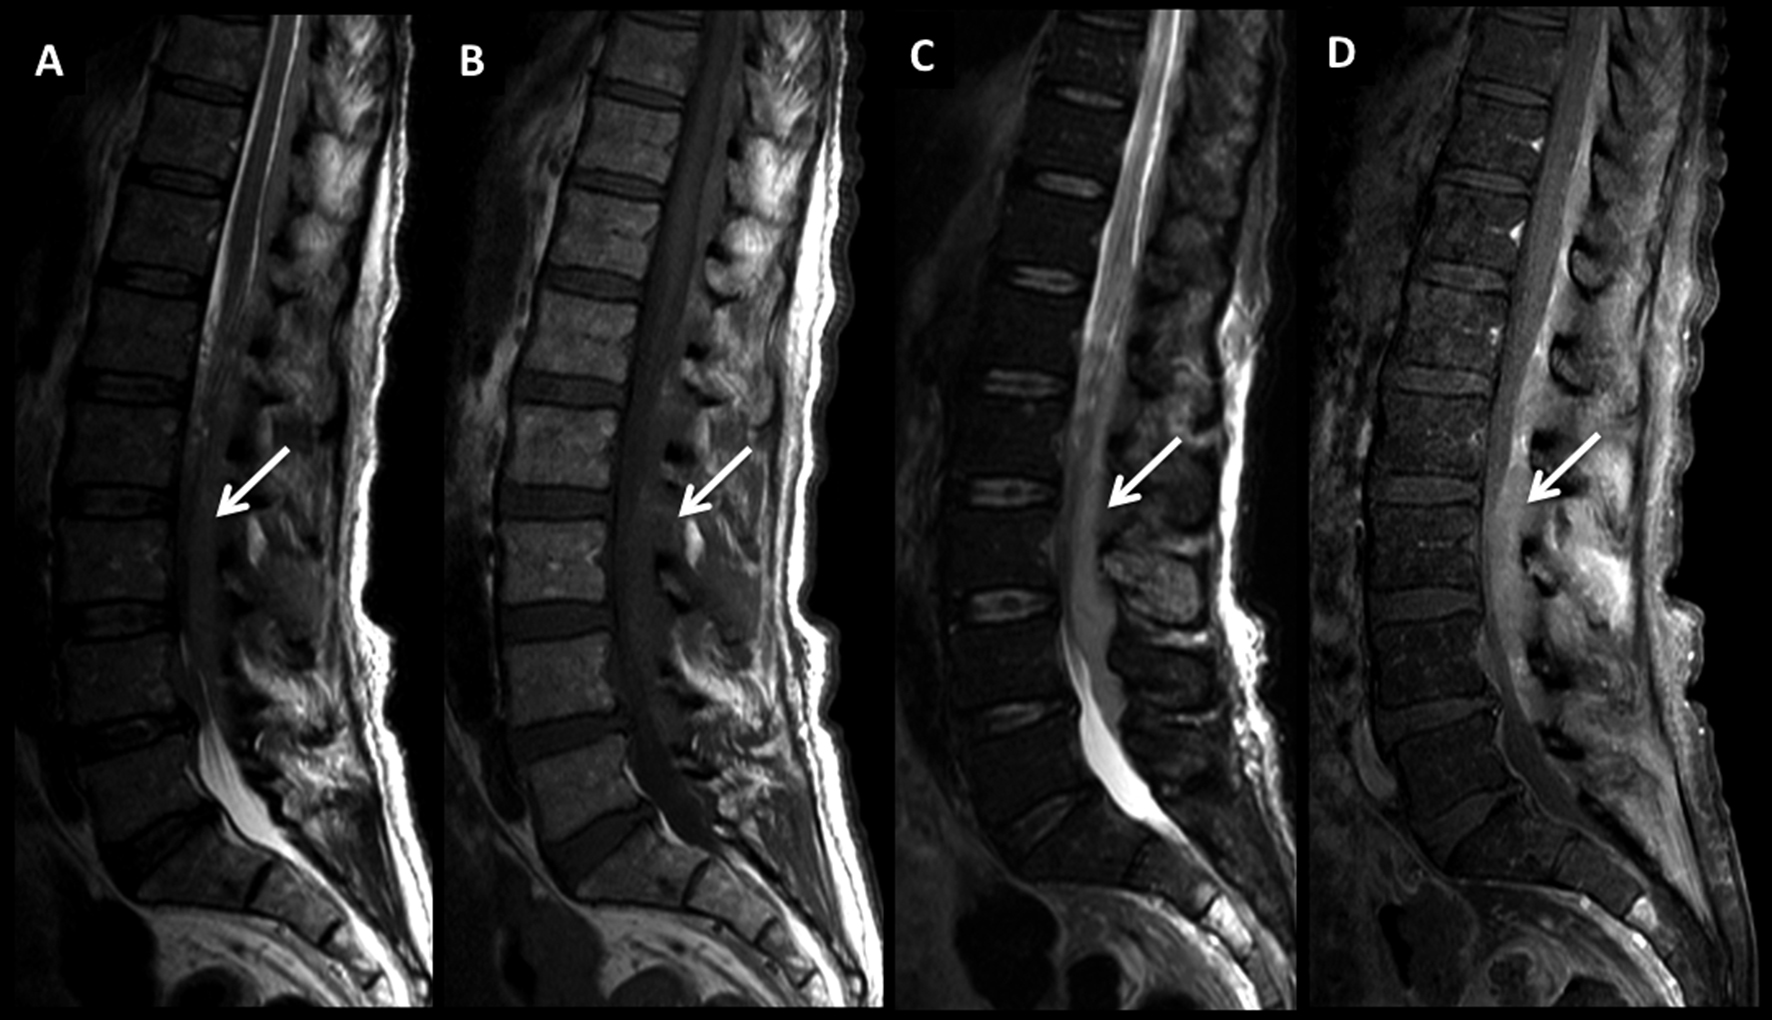

Figura 2

LNH, lesión ósea única, compromiso secundario. (cont)

Paciente con LNH y lesión ósea de sustitución en el cuerpo de L4 confirmada por punción, con aplastamiento y compromiso del canal raquídeo.

En RM, secuencia FSE T2 sagital (A) la lesión es heterogénea, predominantemente de alta señal. Es hipointensa en T1 (B) y tiene intenso realce con el medio de contraste (C).

Es claro el compromiso del muro posterior y la disminución de altura del cuerpo vertebral.

En el plano axial (T1 en D, T2 en E y T1 con contraste en F) se observa la proyección del componente lesional hacia el canal con compromiso severo del mismo (flecha discontínua).

Figura 3

En el paciente se observa un patrón de lesiones múltiples de sustitución con un patrón infiltrativo. En la TC plano sagital (A) se observa un aumento difuso, parcheado de la densidad, sin aplastamientos vertebrales.

En RM, secuencia T2 sagital (B) las lesiones están mal definidas con alta señal, hipointensas en secuencia T1 (C) y edema en secuencia STIR (D).

Este patrón, menos frecuente, tiene diferentes diagnósticos diferenciales, sobre todo con el mieloma múltiple.